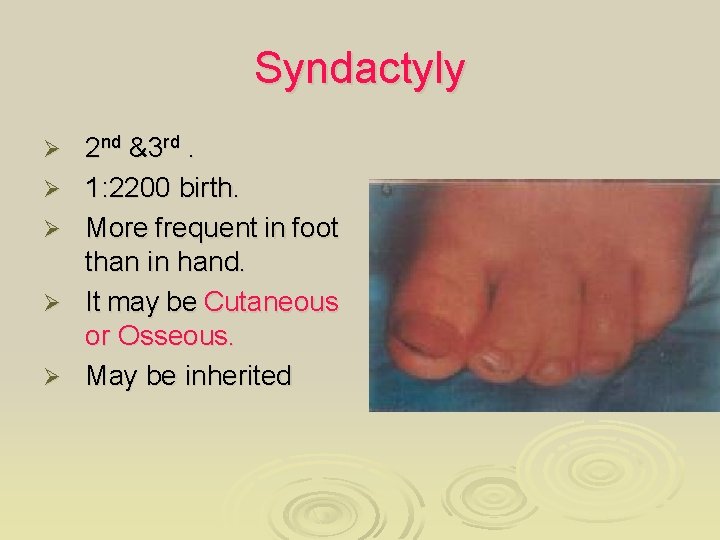

Syndactyly Ø Ø Ø 2 nd &3 rd. 1: 2200 birth. More frequent in foot than in hand. It may be Cutaneous or Osseous. May be inherited